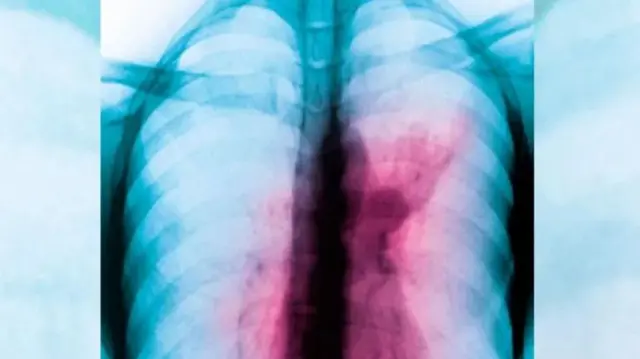

2024 World Tuberculosis Day: Ihe ị kwesịrị ịma maka ụkwara nta

Tuberculosis ka ndị Igbo na akpọ ụkwara nta. Ndị ọkacha mara na ahụ ịke kwụrụ na ọ bụ ọrị na egbuegbu na ọ bụrụ na onye ọ na eme enweteghị ọgwụgwọ ọsịsọ.

Kedụ ka ụkwara nta sịrị egbu mmadu?

Dọkinta Okerịe kwurụ na “Ụkwara nta bụ ọrị kacha emetụta ngụgụ mmadụ. O nwere ịke ịmetụta ịhe ndị ọzọ na ahụ mmadụ dịka ụbụrụ, erịrị afọ nakwa akụkụ ọmụmụ ụmụ nwanyị”.